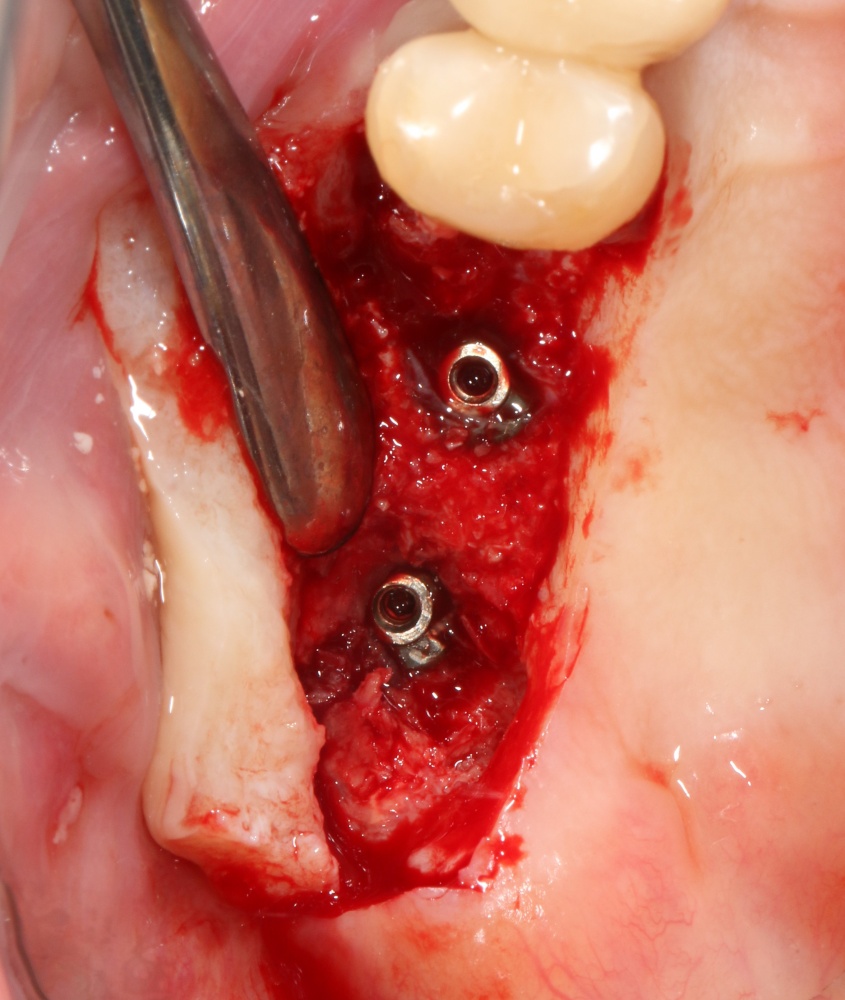

В описываемом клиническом случае нам нужно замещать достаточно большой объем костной ткани, поэтому использование ксенографта (Geistlich Bio-Oss) выглядит совершенно разумным. Мы смешиваем его с аутокостной стружкой, источником клеток и факторов роста костной ткани, в пропорции, примерно 50/50, получая, при этом, около 3 куб см готового к использованию графта:

С помощью него мы «достраиваем» недостающую часть альвеолярного гребня, полностью перекрывая импланты. Напомню, что субкрестальные Ankylos Dentsply Implants вполне допускают такой подход.

Костная ткань, в отличие от слизистой оболочки, регенерирует очень медленно. Если ее не отделить от быстрорастущих тканей, то место, где должна регенерировать костная ткань, быстро заполняется грануляциями — и, в итоге, для кости не остается пространства для роста. Чтобы отделить одно от другого, используются коллагеновые барьерные мембраны.

В нашем случае мы используем Geistlich Bio-Gide. Почему? Потому, что, имхо, это лучшее, что есть на рынке барьерных мембран. Почему? См. RegenerationDay.